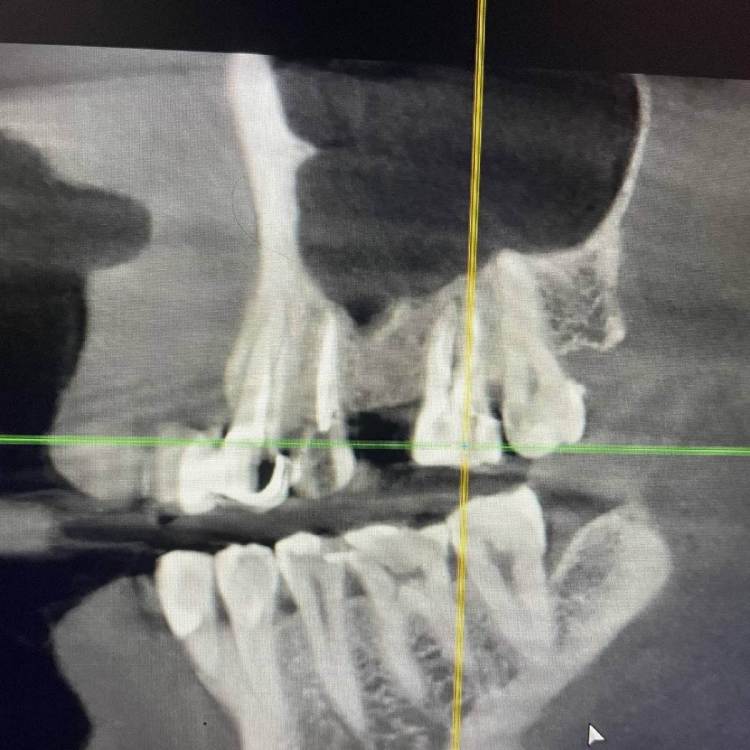

1586Doc Опубликовано 12 мая, 2021 Автор Поделиться Опубликовано 12 мая, 2021 ретрит зубов 15.14.26 и контроль клкт через 6 месяцев Ссылка на комментарий